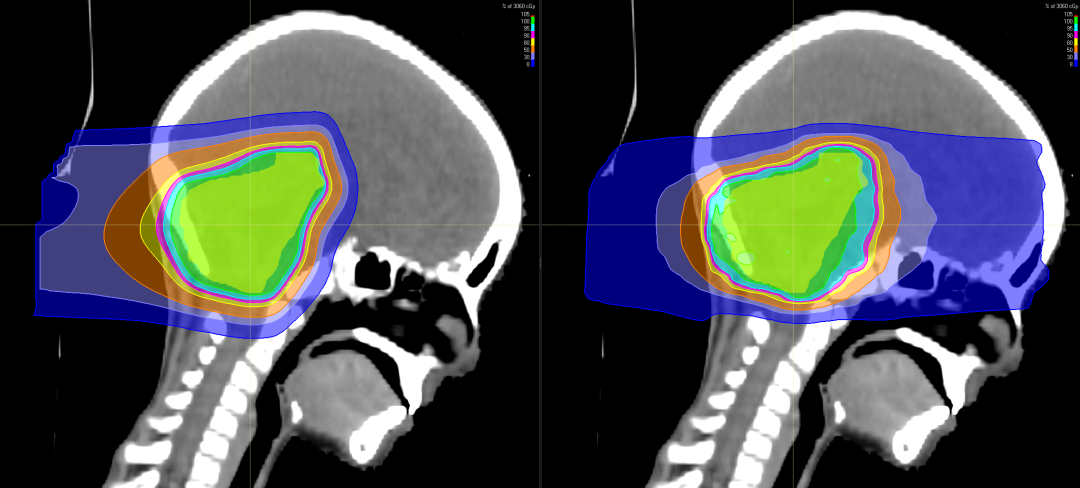

与X线调强放疗(IMXT)相比,笔形束扫描(PBS)质子治疗具有更优的剂量适形性及靶区覆盖情况。

有研究表明,儿童神经母细胞瘤使用质子治疗的最大效益在于减少脑部正常组织构造的损伤,进而降低长期伤害。质子治疗是一种比其他任何形式的放射治疗更准确,更精确地靶向肿瘤,同时保留健康组织,目前全球最先进的一种放疗技术。通过质子治疗,可以最大限度地避免靶标外部的绝大多数不必要的辐射。

与传统形式的辐射相比,质子束会到达肿瘤内部的精准位置而不是沿着光束离开人体的路径释放大部分辐射剂量。实际上,质子没有肿瘤之外的辐射“退出剂量”,这意味着质子停在肿瘤上,不会继续伤害身体的健康部位。

随着儿童癌症治疗进步,儿童的存活率上升,存活下来的儿童患者日后之生活品质越来越受到关注,质子治疗具备能够减少散射剂量的优势,提升对肿瘤局部的控制,同时由于脑部神经组织多,易受辐射损害。质子治疗因具有布拉格峰的物理特性,使峰值部位对准肿瘤病灶处,发出最高剂量,产生最高峰,达到最佳杀瘤效果;峰后剂量趋于零,对周边脑组织几乎无影响。对于儿童脑瘤,可以避免有常规化疗引起的听力丧失、认知功能障碍、智力影响等。